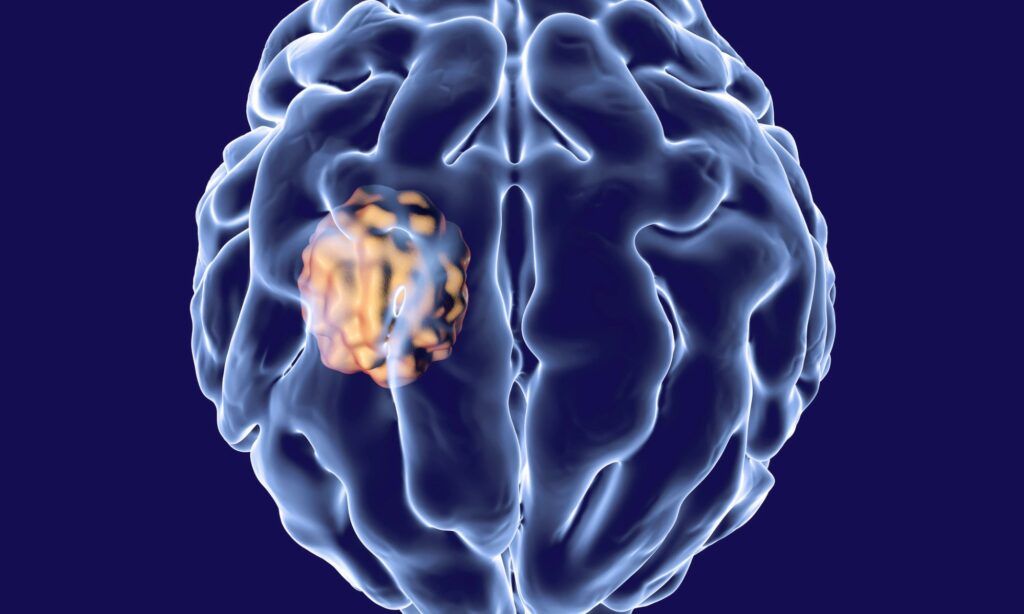

Our professional Kogarah chiropractors assess and provide management of various patient conditions affecting the spine, neck, and back. Whether you’re suffering from acute pain, chronic discomfort, or a sports injury, our clinic specialists will conduct a thorough examination to determine the root cause of your issue. Our practice utilizes cutting-edge diagnostic tools, such as MRI, CT, and X-ray, to identify disc herniation, bulge, or desiccation that may be contributing to your symptoms.

In addition to spinal and muscular conditions, our practice offers specialized care for patients experiencing dizziness, vertigo.